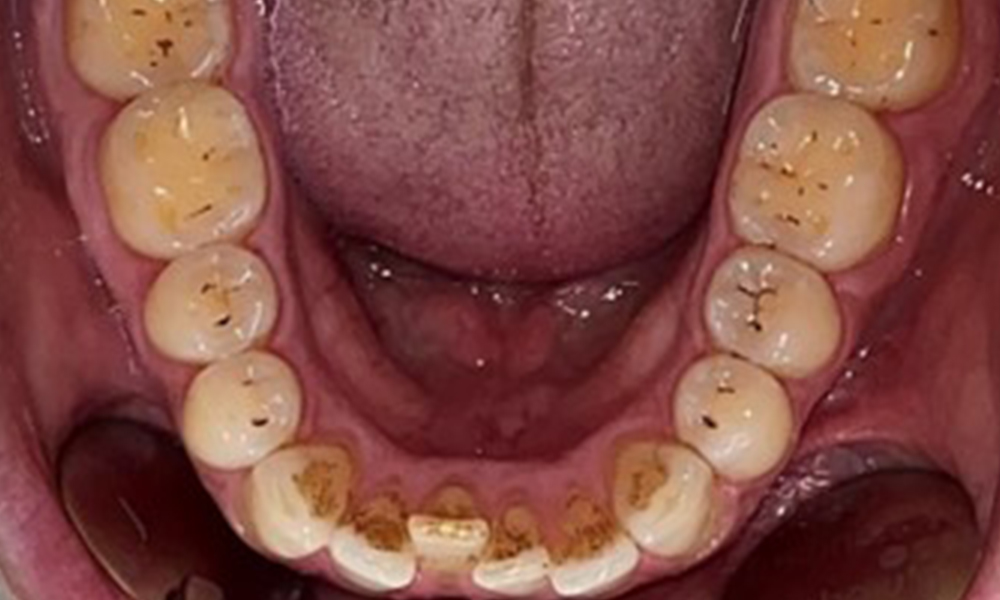

Occlusal view of the mandible, © Dr R. Krapf

Fig. 4: Occlusal view of the mandible, © Dr R. Krapf

Dental findings

The patient has full dentition with a total of 28 teeth. There were noteworthy erosions and attritions. (Fig. 4, Fig. 5). Due to bruxism, the patient has been wearing a splint with an adjusted bite block at night for many years. The erosions were caused by long-term consumption of isotonic beverages. No periodontal bone loss or active caries were observed.